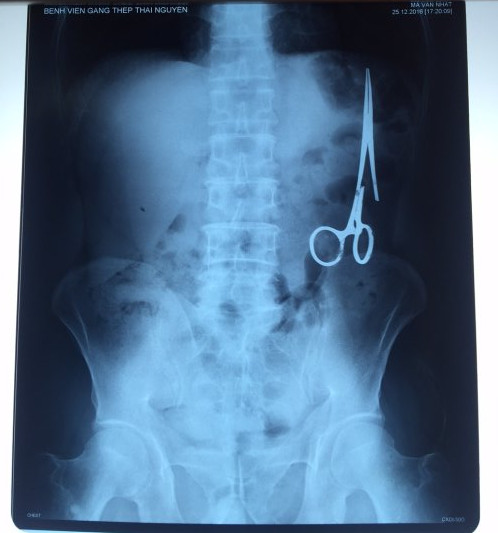

遺留在病人腹中的剪刀

據(jù)越南青年報(bào)1月2日?qǐng)?bào)道,在越南首都河內(nèi)醫(yī)療專家的幫助下,越南東北部的太原?。═hai Nguyen)鑄鋼醫(yī)院的醫(yī)生日前從54歲患者M(jìn).V.N腹中取出一把醫(yī)用剪刀。這把剪刀是此前曾為M.V.N手術(shù)的醫(yī)生遺留的,已經(jīng)在其腹中待了18年時(shí)間。

醫(yī)務(wù)人員表示,這把剪刀遺留在病人腹部左側(cè),與結(jié)腸緊挨著。剪刀的把手已經(jīng)生銹,部分器官也已經(jīng)與剪刀粘連起來。但在過去多年中,M.V.N沒有任何不適感覺,也從未因?yàn)榱粼诟怪械募舻兑l(fā)的相關(guān)問題去看過醫(yī)生。直到2016年12月,M.V.N因?yàn)樵庥隽艘粓鲕嚨?,才到鑄鋼醫(yī)院進(jìn)行身體檢查。

超聲波檢查顯示,M.V.N的腸子中有個(gè)奇怪物體,看起來就像醫(yī)用剪刀。M.V.N證實(shí),他曾于1998年6月份在北江省綜合醫(yī)院接受手術(shù),在此后也從未進(jìn)行過任何手術(shù)。近來,他感到腹部有些疼痛,并試圖通過服用藥物治療。12月27日,M.V.N回到北江省綜合醫(yī)院再次進(jìn)行超聲波檢查,顯示其腹部的確存在怪異物體。